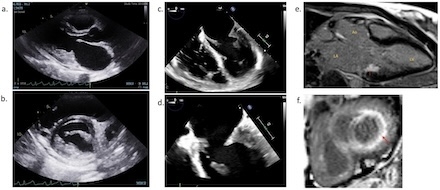

Serologic work-up was consistent with an SLE flair. MRI of the brain/orbits demonstrated two acute infarcts in the frontal and parieto-occipital lobes. CTA head and neck did not show any large vessel vasculitis. Transthoracic echocardiography showed thickening of the mitral valve (MV) leaflets, with moderate MR and an elevated MV gradient of 11 mm Hg. The posterior leaflet was not visualized, concerning for absent or hypoplastic posterior leaflet. A transesophageal echocardiogram was performed and showed severe thickening of posterior mitral leaflet with restricted motion and shortening secondary to extensive thrombus burden. In addition, there was evidence of thrombus at the tip of the anterior MV leaflet. The patient was managed with high dose steroids and warfarin for SLE flair and marantic endocarditis, respectively.

Two months later, she presented with amaurosis fugax. Cardiac MRI showed thickened MV leaflets with delayed enhancement along the posterior leaflet and MV annulus consistent with an organized thrombus. After multidisciplinary discussion, the patient underwent surgical MV replacement with a bioprosthetic valve. Intraoperative evaluation revealed severely thickened MV leaflets with fused commissures. In addition, there was fusion of the posterior leaflet and lateral side of the anterior leaflet to the papillary muscles as a result of thickened and shortened chordae. These findings were believed to be due to inflammatory changes involving the MV apparatus. Surgical pathology confirmed the diagnosis of valvulitis. The patient has done well post operatively.